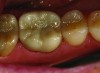

A patient presented with worn dentition, defective amalgam fillings, and visible cracks in the molar regions (Figure 1). The patient, a bruxer, requested a conservative treatment rather than a full-mouth reconstruction to rebuild lost vertical dimension. A treatment plan was proposed to replace the defective amalgams with tooth-colored direct composite fillings, and place full-coverage zirconia Lava™ Plus (3M ESPE, 3mespe.com) crowns where needed. Full-contour zirconia was chosen for the full-crown material based on its strength, minimal reduction requirements, and its ability to provide the desired tooth-colored appearance.

Figure 1: Pre-op photo.

Figure 1